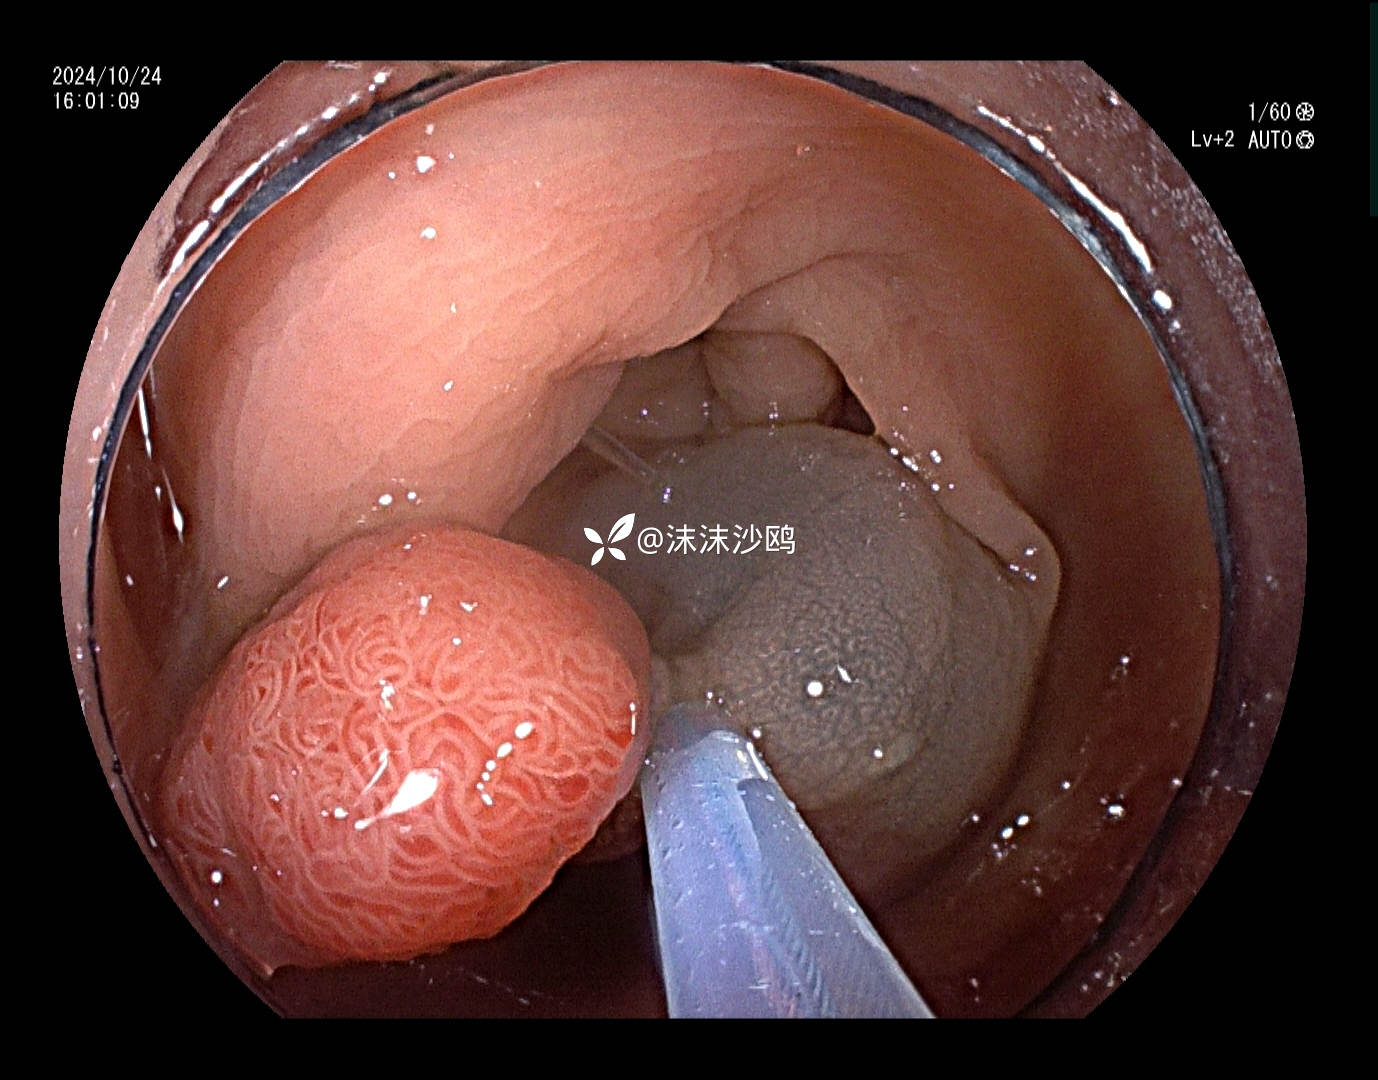

患者去年发现乙状结肠肿瘤同是发现多发腺瘤样隆起,先做了肿瘤切除手术,没有进一步放化疗,现来复查肠镜顺便嘎息肉。翻看之前的肠镜报告,肠道清洁差,发现的息肉就有六七个,应该还有漏掉的。嘱患者肠道一定要清洁到位。今日下午只安排了他一个人的肠镜专场,专门处理他的息肉。

冰山一角,大大小小嘎了十三四个,大的就有六七个,大部分EMR切除。希望术后不要有并发症。